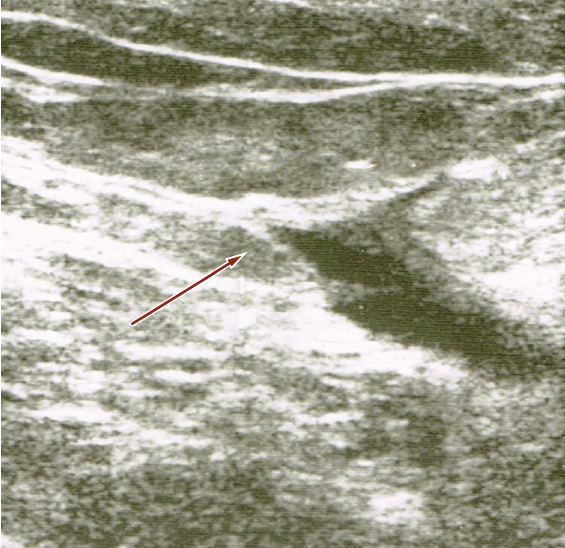

Un’ecografia-Doppler venosa dell’arto inferiore destro rileva materiale trombotico endoluminale nell’asse femoro-popliteo (Figura 1).

Figura 1. Ecografia-Doppler venosa arto inferiore destra (cross safeno-femorale destra)